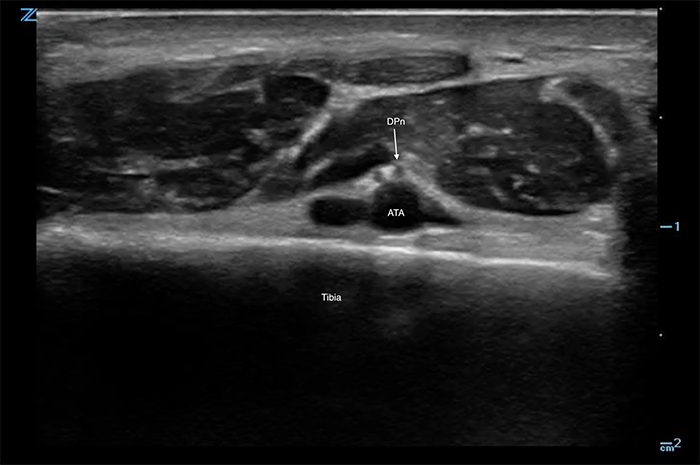

Figure 1. Deep peroneal nerve with anterior tibial artery

- A high-frequency linear array probe is applied in a transverse plane over the anterior ankle immediately above the malleoli.

- Probe indicator is towards the operator's left.

- The anterior tibial artery is the landmark structure for this block.

- Artery is seen deep to the extensor hallucis longus and the anterior tibial tendon.

- At this level the deep peroneal nerve is commonly lateral to the artery but can be anterior or medial.

- If the nerve is not seen, quickly sliding the probe along the course of the artery may highlight the nerve.

- If the nerve is still not seen, the target of the block is to inject around the artery.